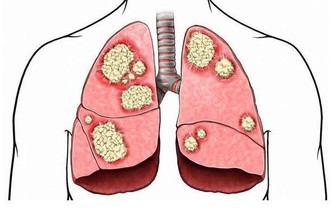

環境中的污染氣體吸收到了身體裡沒有排出去,這些一點點累積,就成了身體毒素。

綜上所述,身體毒素會對身體健康構成很大的威脅,很多疾病都與身體毒素息息相關。